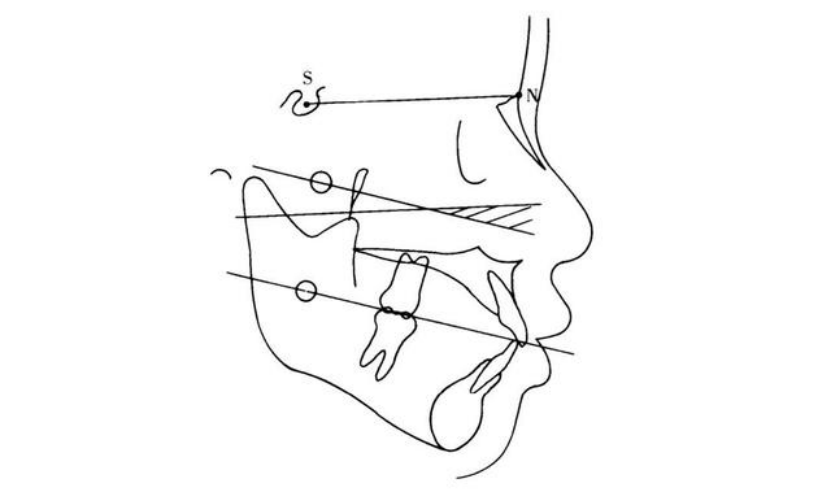

口腔正畸行业发展至今,学者们通过对X线头侧片进行描图、定点和连线,将三维的颅面结构转化为二维平面图形,进行各种线距、角度、比例、弧形的分析,形成了多种分析方法!每种分析方法各有侧重,但在全面分析颅、颌、牙、面硬软组织结构关系变化方面,辅助指导正畸治疗的目的是一致的。临床医师们可根据自己的喜好和实用要求选择,这里给大家介绍一些常用的较为系统的测量分析方法。Downs分析法同Northwestern分析法一起被认为是所有X线头影测量分析法的基础。由Downs W. B. 于1948年提出,大致分为骨性测量和牙性测量。以眶耳平面作为基准平面,具体包括以下测量内容:骨性测量:包括面角、颌凸角、上下牙槽座角、下颌平面角及Y轴角等5项。1、面角面平面与眶耳平面相交的下后角,代表下颌的突缩程度。角越大,表示下颌越前突;角越小,表示下颌越后缩。

2、颌凸角NA与PA延长线的交角,代表面部的上颌部对整个面部侧面的关系。

3、上下牙槽座角

AB或其延长线与面平面的交角,代表上下牙槽基骨间的相互位置关系。

4、下颌平面角下颌平面与眶耳平面的交角。

5、Y轴角Y轴与眶耳平面相交的下内角,代表面部的生长发育方向。表示颏部的突缩。

牙性测量:包括牙合平面角、上下颌中切牙角、下颌中切牙-牙合平面角、下颌中切牙-下颌平面角及上颌中切牙突距等5项。1、牙合平面角牙合平面与眶耳平面的交角,代表牙合平面的斜度。角越大,代表牙合平面越陡,为安氏Ⅱ类面型倾向;角越小,代表牙合平面越平,为安氏Ⅲ类面型倾向。

2、上下颌中切牙角上下颌中切牙牙长轴的交角,代表上下颌中切牙间的突度关系。角越大,表示突度越小;角越小,突度越大。

3、下颌中切牙-下颌平面角下颌中切牙长轴与下颌平面的交角。

4、下颌中切牙-牙合平面角下颌中切牙长轴与牙合平面相交的下前角。

5、上颌中切牙突距上颌中切牙切缘至AP连线的垂直距离,代表上颌中切牙的突度。当上颌中切牙切缘在AP连线前方时为正值,反之为负值。

Wits分析法由Jacobson于1975年提出,Wits是美国Witwatersrand大学校名缩写。Wits分析法用于测量上、下颌骨前部的相互关系。Jacobson在他设计的新方法中,没有使用SN平面作为基准平面,而代之以功能牙合平面作为基准平面。具体方法如下:由A、B点向功能牙合平面作垂线,得Ao、Bo点,测Ao-Bo距离以反应上下颌骨前部的相互关系。当Ao在Bo前方时,值为正,反之为负,两点重叠值为零。

Jacobson研究认为:女性Wits值为0,男性Wits值为-1。当Wits值过大时,表示Ⅱ类骨性错牙合关系;当Wits值过小时,表示Ⅲ类骨性错牙合关系。Tweed分析法也被称作Tweed三角分析法,主要测量由眼耳平面、下颌平面和下中切牙长轴所组的三角形构成。由于其定点简单、直观、易测,目前为临床医生做常规头影测量分析时,特别是判断拔牙及预后侧貌评估中广为应用的一种方法。

a.眶耳平面-下颌平面角:眶耳平面与下颌平面的交角,以下颌下缘的切线作为下颌平面。b.下颌中切牙-眶耳平面角:下颌中切牙长轴与下颌平面的交角。c.下颌中切牙-下颌平面角:下颌中切牙长轴与下颌平面交角。在Tweed分析法中,不论错牙合畸形的部位在哪,均以下颌的分析为依据。Tweed认为,FMIA 65°是建立良好面型的重要条件,因而FMIA 65°称为矫治追求目标。以上介绍的几种X线头影测量分析法,是目前在正畸临床应用比较广泛的。您临床常用的是哪种分析方法呢?